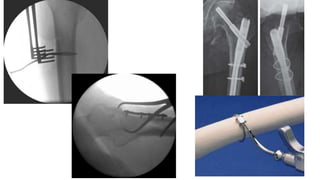

•Tracción

•Herramienta F

•Ayuda de

reducción

intramedular

Core Curriculum V5

Reducción Cerrada

Reducción Abierta

• Minimamente Invasiva

• Hook

• Pin de Schanz

• Clamps(weber,colinear)

• Alambre

• Picador

• Elevador de Cobb

• Pinzas para hueso

• Pinzas Quirurgicas

• Placas

Técnicas de Reducción